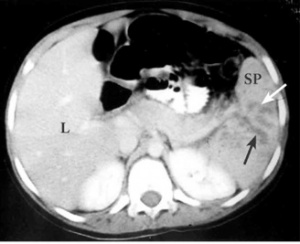

# טומוגרפיה ממוחשבת הינה אמצעי חשוב ביותר לאבחון של קרעים בטחול של חולה יציב. בטומוגרפיה ממוחשבת ניתן לראות את אופי הקרע, את כמות הדם בבטן וגם ניתן לקבל מידע על נזק לאיברים אחרים (תצלומים 1-2.11). ב- CT ניתן לראות גם דלף של חומר ניגוד המוזרק דרך הווריד במהלך הבדיקה אל מחוץ לטחול. דלף זה הוא סימן חשוב לדימום פעיל מהטחול ומהווה הוריה יחסית לניתוח של החולה. | # טומוגרפיה ממוחשבת הינה אמצעי חשוב ביותר לאבחון של קרעים בטחול של חולה יציב. בטומוגרפיה ממוחשבת ניתן לראות את אופי הקרע, את כמות הדם בבטן וגם ניתן לקבל מידע על נזק לאיברים אחרים (תצלומים 1-2.11). ב- CT ניתן לראות גם דלף של חומר ניגוד המוזרק דרך הווריד במהלך הבדיקה אל מחוץ לטחול. דלף זה הוא סימן חשוב לדימום פעיל מהטחול ומהווה הוריה יחסית לניתוח של החולה. | ||

| − | + | [[קובץ:קרעטחול1.jpg|מרכז|ממוזער|תצלום 1.11: קרע של הטחול במרכז. החצים מצביעים על אזור הקרע; SP - טחול; L - כבד]] | |

- טומוגרפיה ממוחשבת הינה אמצעי חשוב ביותר לאבחון של קרעים בטחול של חולה יציב. בטומוגרפיה ממוחשבת ניתן לראות את אופי הקרע, את כמות הדם בבטן וגם ניתן לקבל מידע על נזק לאיברים אחרים (תצלומים 1-2.11). ב- CT ניתן לראות גם דלף של חומר ניגוד המוזרק דרך הווריד במהלך הבדיקה אל מחוץ לטחול. דלף זה הוא סימן חשוב לדימום פעיל מהטחול ומהווה הוריה יחסית לניתוח של החולה.